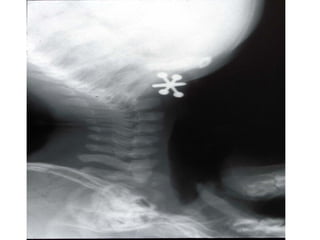

Epiglottitis  is inflammation of the epiglottis typically caused by a bacterial infection that may cause it to swell and block the airway.

Child with epiglottitis  getting an X ray

Epiglottitis isinflammation of the epiglottis typically caused by a bacterial infection that may cause it to swell and block the airway.